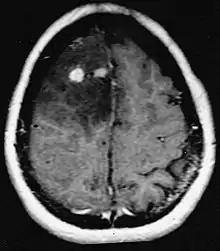

Le lymphome primitif du système nerveux central représente environ 2 pour cent à 3 pour cent de toutes les tumeurs cérébrales chez les patients ayant un système immunitaire normal. Ils surviennent plus fréquemment chez les hommes de plus de 55 ans jusqu'à 60 ans. Près de la moitié de tous les lymphomes surviennent chez des patients de plus de 60 ans et environ un quart chez des patients de plus de 70 ans. L'incidence semble augmenter avec l'âge, mais la raison n'est pas encore claire. Les patients dont le système immunitaire est affaibli sont plus à risque de développer un lymphome du SNC, de sorte que ceux qui ont subi une greffe d'organe ont une immunodéficience congénitale ou une maladie auto-immune, ou sont infectés par le virus de l'immunodéficience humaine. Les lymphomes cérébraux associés au VIH sont associés au virus d'Epstein-Barr, en particulier chez les patients dont le nombre de lymphocytes CD4 est inférieur à 500 cellules par millimètre cube dans le sang. La plupart des lymphomes du SNC sont des lymphomes diffus à grandes cellules B.

Les patients souffrent d'une variété de symptômes caractéristiques d'une lésion massive focale ou multifocale. L'IRM montre généralement des tumeurs avec un rehaussement de contraste homogène au sein de la substance blanche périventriculaire profonde. La multifocalité et le rehaussement inhomogène sont typiques des patients dont le système immunitaire est affaibli. L'analyse du lymphome du SNC est extrêmement importante dans le diagnostic différentiel de la néoplasie cérébrale. Il est à noter que l'administration de corticoïdes peut entraîner la disparition complète du rehaussement, rendant difficile le diagnostic des lésions. Par conséquent, si un lymphome du SNC doit être pris en compte dans le diagnostic différentiel, les corticoïdes doivent être évités à moins que l'effet de masse ne provoque un problème grave et immédiat chez le patient.

Les métastases cérébrales sont les néoplasmes intracrâniens les plus courants chez les adultes, étant dix fois plus fréquents que les tumeurs cérébrales primaires. Ils marchent à 20 jusqu'à 40 pour cent des adultes atteints de cancer et sont principalement associés au cancer du poumon et du sein et au mélanome . Ces lésions résultent de la propagation des cellules cancéreuses dans la circulation sanguine et surviennent le plus souvent à la jonction de la matière grise et blanche, où la section transversale des vaisseaux sanguins change, emprisonnant les embolies de cellules tumorales . 80 % des lésions surviennent dans les hémisphères cérébraux, 15 pour cent dans le cervelet et 5 pour cent dans le tronc cérébral. Environ 80 % des patients ont des antécédents de cancer systémique et 70 pour cent ont de multiples métastases cérébrales.

Des progrès significatifs ont récemment été réalisés dans le diagnostic et le traitement de ces lésions, entraînant une amélioration de la survie et du contrôle des symptômes. L'apparition des signes et des symptômes est similaire à celle d'autres lésions massives du cerveau. La méthode de diagnostic de choix est l'imagerie par résonance magnétique utilisant des produits de contraste.